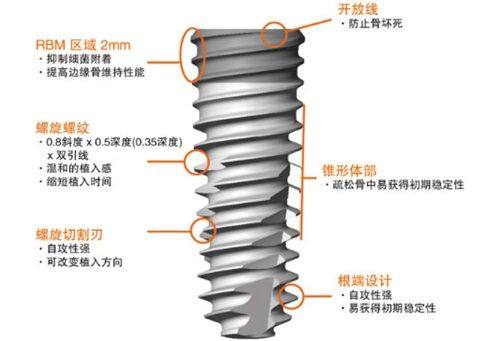

嘿,想了解韩国美格真种植牙的宝子看过来!韩国美格真种植牙属于二线品牌,它有20多年研发历史,在市场上表现不错。韩国美格真种植牙齿的寿命一般能达到10 - 15年,很多案例显示其耐用性良好。韩国美格真种植牙一颗价格在4000 - 8000元左右。到2025年,这个品牌或许会有更多惊喜。想冲的朋友先看完再决定!

资讯为什么医生不建议选择韩国品牌的种植牙?因其对牙槽骨要求高、临床数据少、材料工艺有局限及个体适配性差

家人们,我最近想种牙,听说很多医生不建议选韩国品牌的种植牙,这是为啥呀?其实是因为韩国种植牙对牙槽骨条件要求高、临床数据支持不足、材料与工艺有局限,还有个体适应性问题。那韩国的种植牙体不好吗,为啥便宜呢?资料没说便宜原因,但也不能简单说它不好。韩国种牙植体质量又咋样?材料和稳定性方面有提升空间。想了解更多细节,接着看正文哟!